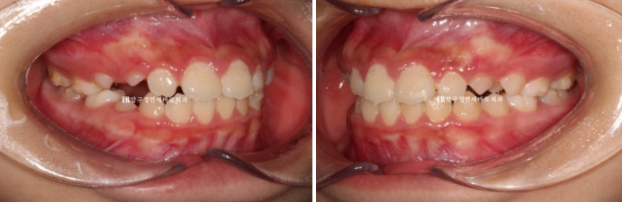

23년 10월 만 11세 친구가 교정을 위해 첫 내원을 했습니다.

보호자가 보기에 가장 고치고 싶은 것은 돌출이고 앞니 사이즈가 큰 편 입니다.

23.10

파란 화살표 측절치 치아는 아래와 거꾸로 물리는 반대교합입니다.

윗니 뻗침 즉 돌출 때문에 입술이 잘 안 다물어지는 입술부전증의 결과로 턱끝 근육이 울퉁불퉁하게 주름이 잡히는 호두턱 호두주름도 있습니다.